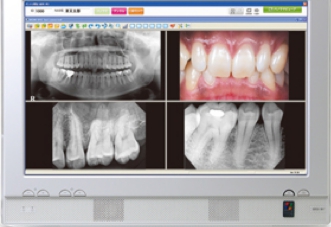

CTスキャン検査

インプラント(人工歯根)治療を適切に行うためには、顎の骨の状態を詳しく調べることが重要です。

そこで、CTスキャン検査を行うことによって顎の骨の断面画像を撮影し、その画像を見ながら治療の計画を立てます。より安全で、無理の無い治療を受けることが出来る最新の方法です。

当院でCTを撮り、コンピュータを使って画像診断をし、精度の高い検査を実施しております。

この検査の結果に基づいて、最適なインプラント治療の計画を立て、十分に納得していただけるようご説明いたします。